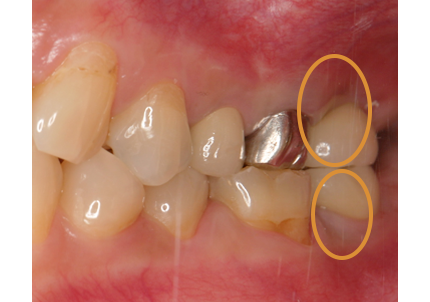

3.右上インプラント補綴物装着(2009年7月24日)

↑ 右上サイナスリフト後にインプラント埋入

4.左上下7番インプラント補綴物装着(2010年5月24日)